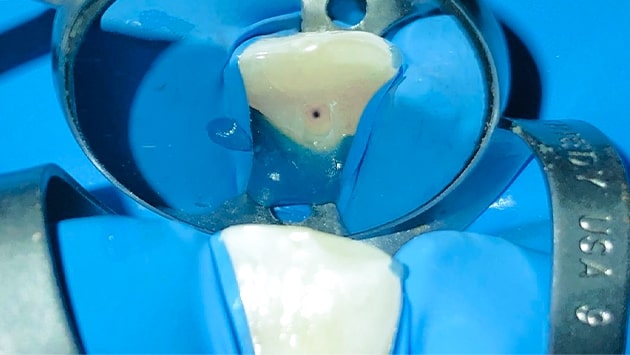

At X dentistry Tijuana we treat dental cavities following four simple steps that will be explained as it follows:

State-Of-The-Art Technology For

Root Canal In Tijuana

By incorporating advanced technologies, XDentistry ensures that root canal treatments are not only efficient but also highly precise, tailored to each patient’s unique dental needs. This commitment to cutting-edge advancements guarantees optimal outcomes and patient satisfaction.

3D CBCT for Teeth Scanning:

Providing detailed 3D images of the teeth and surrounding structures. This aids in diagnosing complex root canal cases by offering a comprehensive view, enabling precise treatment planning.